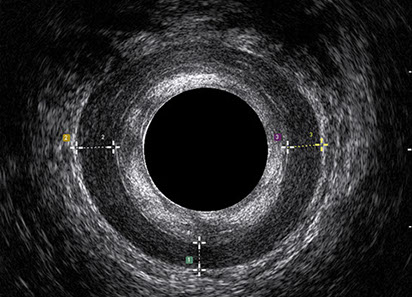

L’ecografia transanale permette di distinguere la sottomucosa che riveste il canale anale, lo sfintere anale interno, e lo sfintere anale esterno.

Le principali indicazioni all’esecuzione di tale esame sono lo studio dell’integrità delle strutture muscolari nei casi di incontinenza fecale, lo studio topografico dei processi settici perianali (ascessi e fistole) e lo studio dei processi proliferativi epiteliali (carcinoma anale).